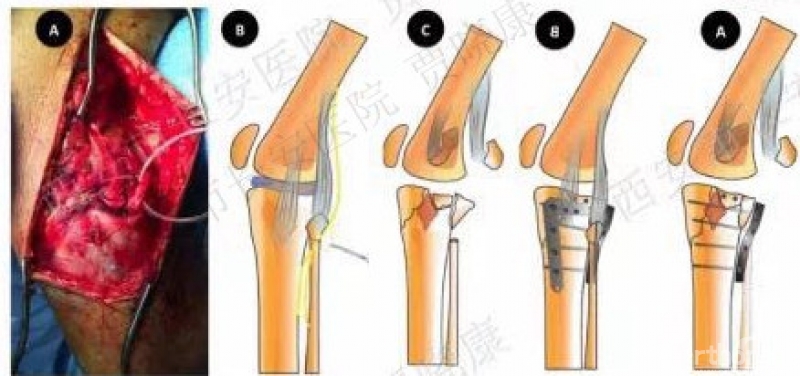

6. 后内L形入路

2010年罗从风

该方法:显露后柱。

适用于:41B2.3x或w、41B3.2x或w、41B1.2可:41B2.1x或u

原文:后外侧入路支撑钢板固定治疗11例胫骨平台后侧劈裂骨折患者。结论:后外侧入路支撑钢板固定是治疗胫骨平台后侧劈裂骨折的一种有效方法,但要熟悉腘窝区解剖结构,正确掌握手术适应证。

7. 改良的后L形入路

2008年王秋根

适用于41B2.1x或u,41B3.1x或u。

原文:改良后外侧入路有助于扩大此类骨折的最佳手术选择,直视下将后外侧剪切骨折的修复固定。